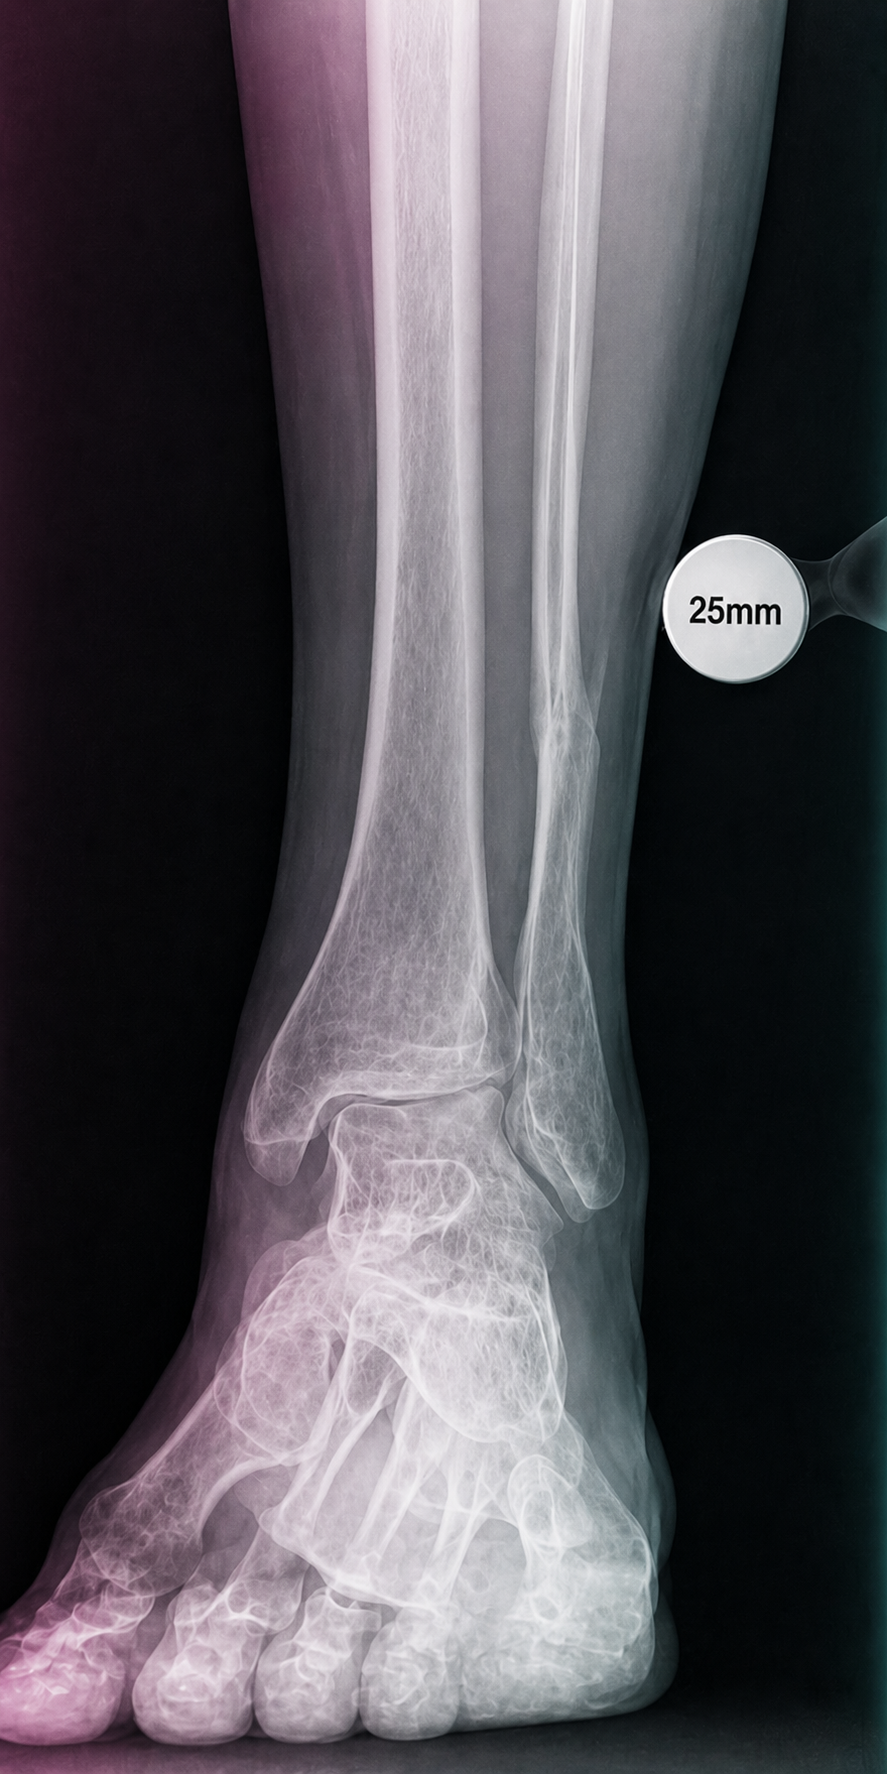

A compact guide for radiology teams on correct calibration sphere placement in orthopedic X-ray imaging. The marker must be positioned in the anatomical plane of the target joint so that digital scaling, measurements and preoperative templating remain clinically reliable.